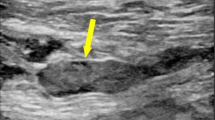

Endpoint events

The endpoint event in this study was DVT before operation. We used Doppler ultrasonography to diagnose the DVT. The diagnostic criteria are the presence of a constant intraluminal filling defect. Patients were examined preoperatively. All patients underwent ultrasonography of bilateral lower extremities the day before the scheduled surgery.